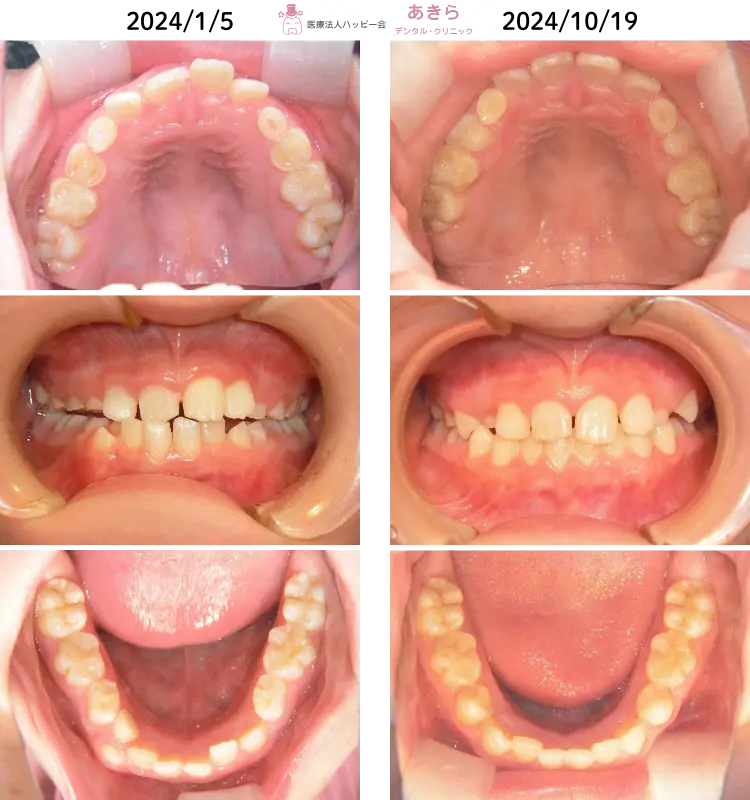

初診 … 2024年1月5日 ⇒ 2024年10月19日

8歳11ヶ月 ⇒ 9歳8ヶ月

2024年1月5日 ⇒ 2024年10月19日(2024年3月プレオルソスタート)

※反対咬合で下顎の偏位と前歯部咬耗を伴うケースでした。このまま放置すると将来的リスクが大きくなるようなケースでした。

⇒ 永久歯前歯部の早期喪失・顎関節への負担増など …

本人の頑張りと努力で早期に正中が合い、噛み合わせが改善されました。

前歯・奥歯が上手く使用できるようになり、食欲も増し顔貌も左右対称になってきております。